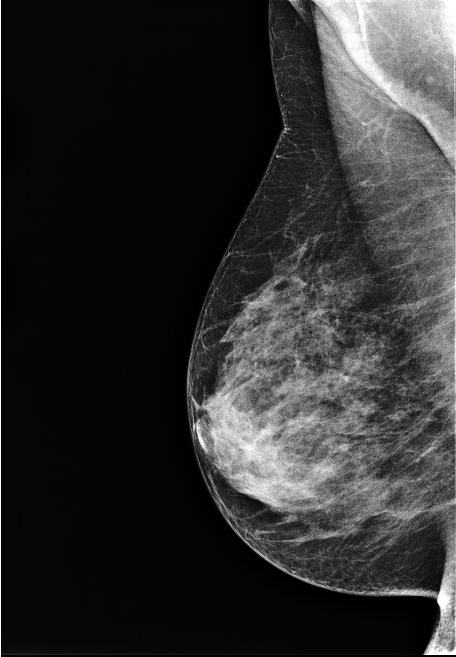

La mammographie est une exploration des seins utilisant les rayons X. Elle est réalisée sur un appareil spécifique situé dans un local exclusivement destiné à cet examen.

La technique utilisée est celle de la radiographie, mais avec un faisceau de plus faible énergie (baisse du kilovoltage).